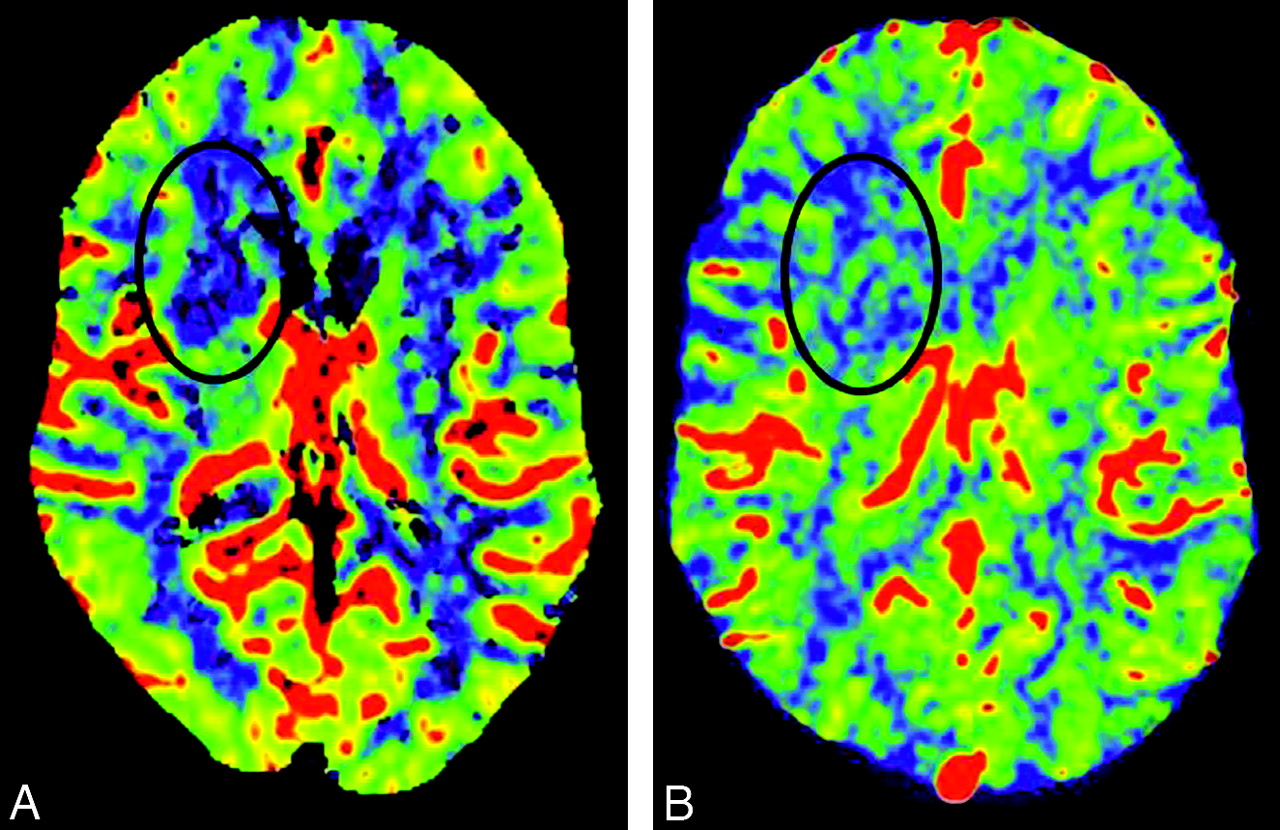

CT (A) and FD-CT (B) show the good correlation of CBV color maps. CTA (C) and FD-CTA (D) display a high-grade stenosis (black arrows) of the left MCA (patient 4). Note the perfect delineation of this high-grade stenosis in FD-CTA.

Using our technique for timing the contrast bolus for the FD-CBV acquisition (bolus watching), all acquisitions were successful. None had to be repeated. It was feasible to measure CBV in all FD-CBV data sets so that both the CTP-CBV and the FD-CBV image and data quality were suitable for evaluation in all patients. There was good correlation of CBV color maps between FD-CBV and CTP-CBV (Fig 2A, -B). Abnormalities were found on the CBV maps from both modalities in 2 of the 10 patients (patient 3, 7). In these 2 patients, CBV abnormalities were secondary to ischemia. In 1 additional patient (patient 8), a CBV abnormality was detected on the FD-CBV map. The CBV maps from the CTP study did not include this area of the brain (temporal lobe), thus making it impossible to compare these 2 studies. The results from the CBV studies in these 3 patients are given in the Table. In patient 8, the CBV value within the lesion was 1.6 mL/100 mL; in the same region of the opposite hemisphere, it was 3.1 mL/100 mL. A subsequent CT scan confirmed an infarct in the region of abnormality seen on the FD-CBV map.

The Bland-Altman test33 in Fig 1B showed that the mean difference of CBV values between FD-CT and CTP was 0.04 ± 0.55 mL/100 mL, meaning that FD-CBV values were slightly higher than CTP values. The mean and SD of the CBV values in each of the 6 anatomic regions among the 10 patients are shown in Fig 1C. The mean values show only minimal differences, and the SDs overlap widely. The correlation coefficient between the CTP-CBV and FD-CT CBV values of all the regions of interest was 0.72 (P < .001).

A 50-year-old man (patient 7) presenting with signs of a right MCA stroke was admitted as an emergency (Figs 3 and 4). CT, CTA, and CTP-CBV revealed a high-grade MCA stenosis and a decrease in CBV in the region of the anterior limb of the internal capsule. MR imaging 24 hours later demonstrated a region of ischemic injury involving the anterior limb of the internal capsule matching with the CBV deficit seen on the CTP-CBV examination. DSA and FD-CTA performed 24 hours after admission confirmed a high-grade M1 stenosis. The area of infarction was faintly visible on the FD-CT; however, the FD-CTA clearly demonstrated the high-grade MCA stenosis and the FD-CBV map was identical to that obtained with the CTP-CBV technique. Measurement of CBV values of the affected region was 1.8 mL/100 mL in the CTP-CBV study and 2.1 mL/100 mL in FD-CT CBV study.

A and B, Comparison of CTP-CBV (A) with FD-CBV (B) demonstrates decrease of CBV in the region of the internal capsule, anterior limb. C, The region matches nicely with the MR image (Fig 3C).